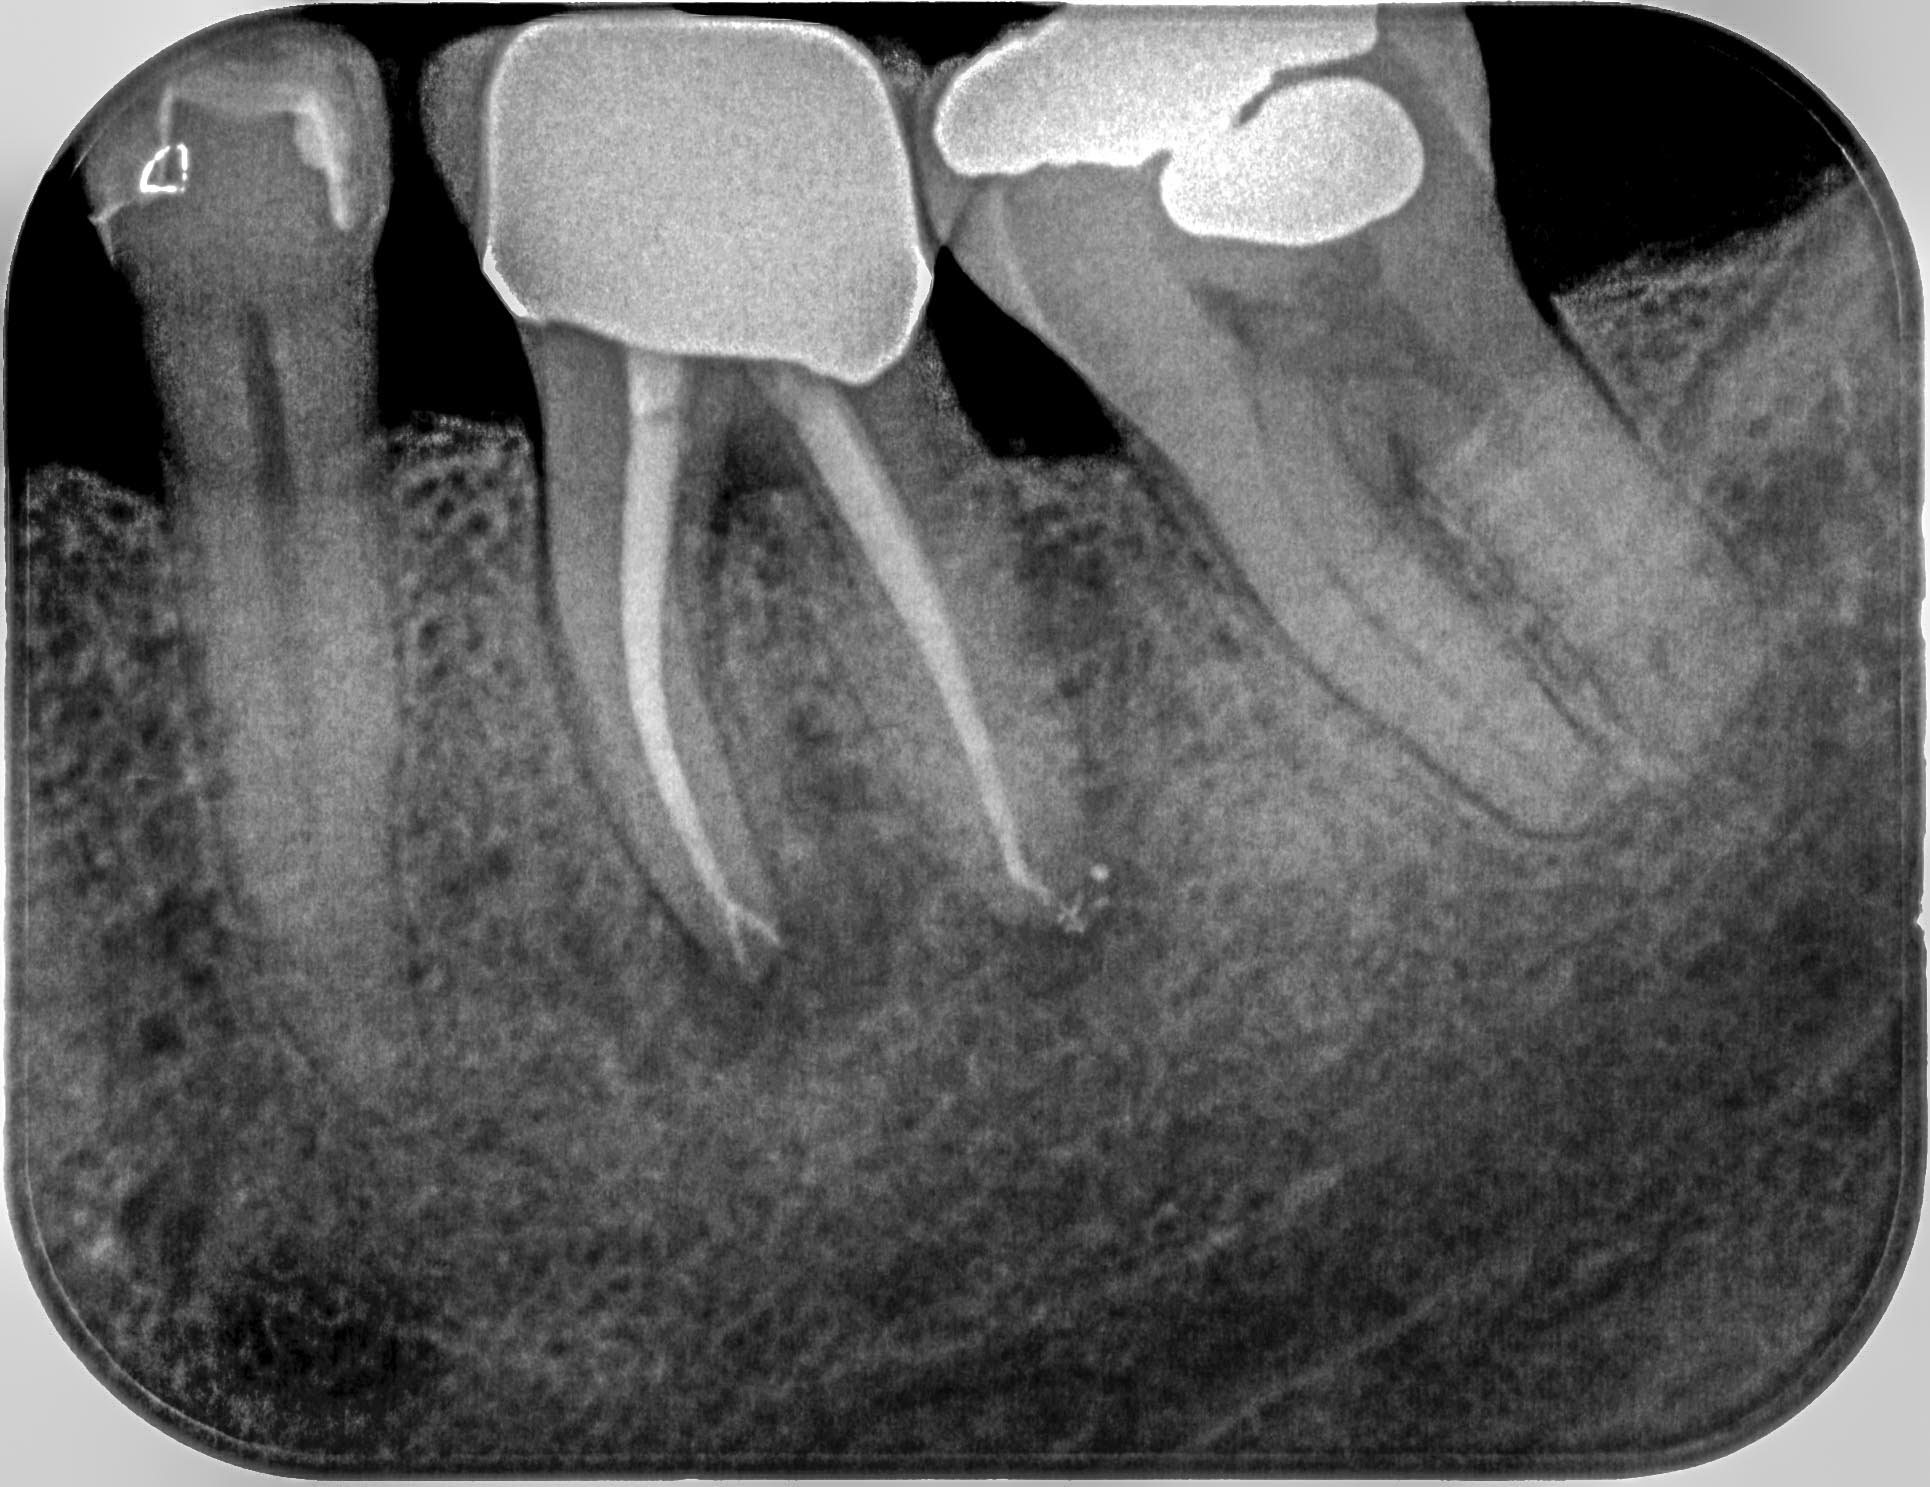

Distal-3 Veröffentlicht 16. Mai 2016 am 1930 × 1487 in Starker distaler Knocheneinbruch – Lohnt der Versuch eines Zahnerhaltes ? Zahn 36 6 Monate post WF Mai 2016